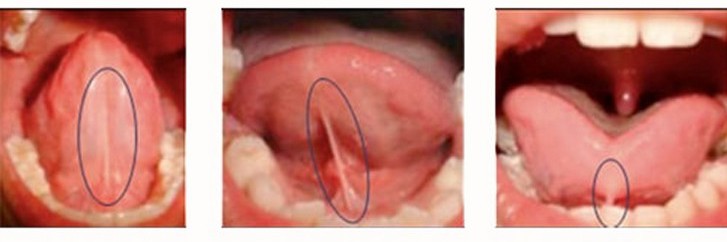

Когда уздечка имеет патологии развития, нарушается нормальное функционирование ротовой полости. В норме она располагается посредине языка и имеет длину около 2,5-3 см, у малышей до года – 8 мм. Обычно аномалии уздечки заключаются в укорочении длины или прикреплении ее к кончику языка. Такое отклонение называется анкилоглоссией, или короткой уздечкой. Характерное для этой аномалии расположение уздечки во рту показано на фото.